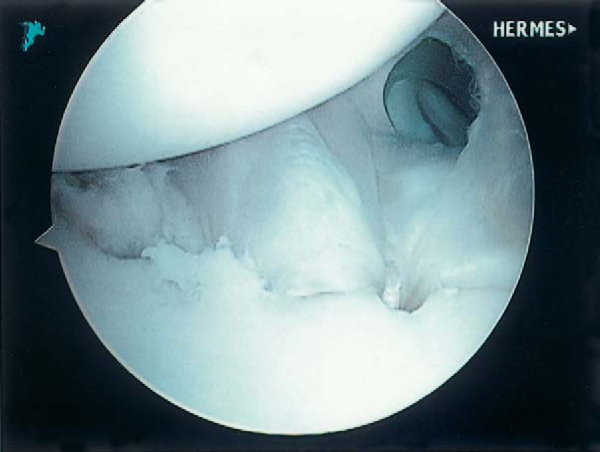

After arthroscopic Bankart repair with the knotless suture anchor, increased superior capsular shift is attained compared with a standard suture anchor, as the knotless anchor pulls the ligament into the drill hole (

Fig. 4-18

). The problems associated with tying knots, knot loosening, and complex suture management are eliminated. Suture strength is improved compared with standard suture anchors. Furthermore, satisfactory results are attained with a low recurrence rate, minimal loss of motion, and reliable functional return, even in contact and collision athletes (